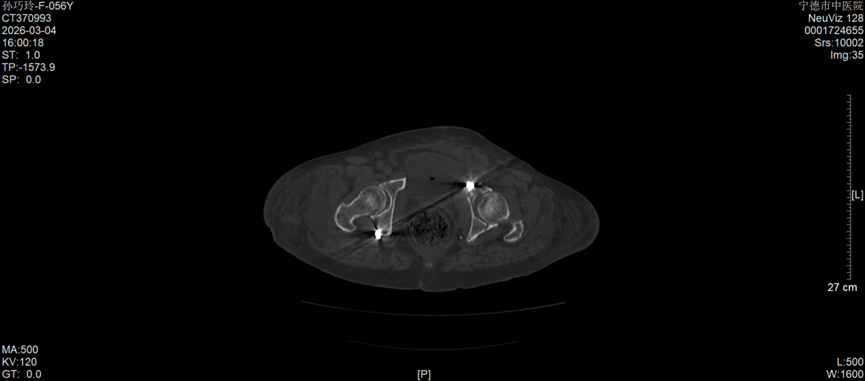

今年57岁的孙女士,因车祸外伤被紧急送往宁德市中医院创伤骨科就诊,经检查确诊为右侧髋臼后壁骨折伴股骨头后脱位,左侧髋臼T形骨折且累及四边体。据了解,髋臼骨折多由高能量损伤引发,其解剖结构复杂,毗邻重要血管神经,复位精度要求高、手术风险大,一直是创伤骨科领域的高难度手术,而双侧髋臼骨折更是该领域中极具挑战性的病例,不仅创伤重、术中出血风险高,诊疗难度也大幅提升。更为棘手的是,孙女士还合并有严重糖尿病及Ⅰ型呼吸衰竭,这无疑进一步增加了病情的复杂性和诊疗的艰巨性。

手术过程中,创伤骨科团队凭借扎实的解剖知识和娴熟的手术操作技巧,小心翼翼地进行组织精细分离,精准完成骨折复位,随后顺利实施牢靠的内固定操作,全程注重保护周围神经血管,严格控制术中出血和组织损伤。得益于周密的术前方案和精准的术中操作,此次手术总出血量控制在传统单侧髋臼骨折手术的常规水平,手术进展顺利。